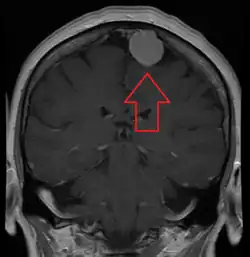

MRI image of a meningioma with contrast

Meningiomas are visualized readily with contrast CT, MRI with gadolinium,[23] and arteriography, all attributed to the fact that meningiomas are extra-axial and vascularized. CSF protein levels are usually found to be elevated when lumbar puncture is used to obtain spinal fluid. On T1-weighted contrast-enhanced MRI, they may show a typical dural tail sign absent in some rare forms of meningiomas.[18]